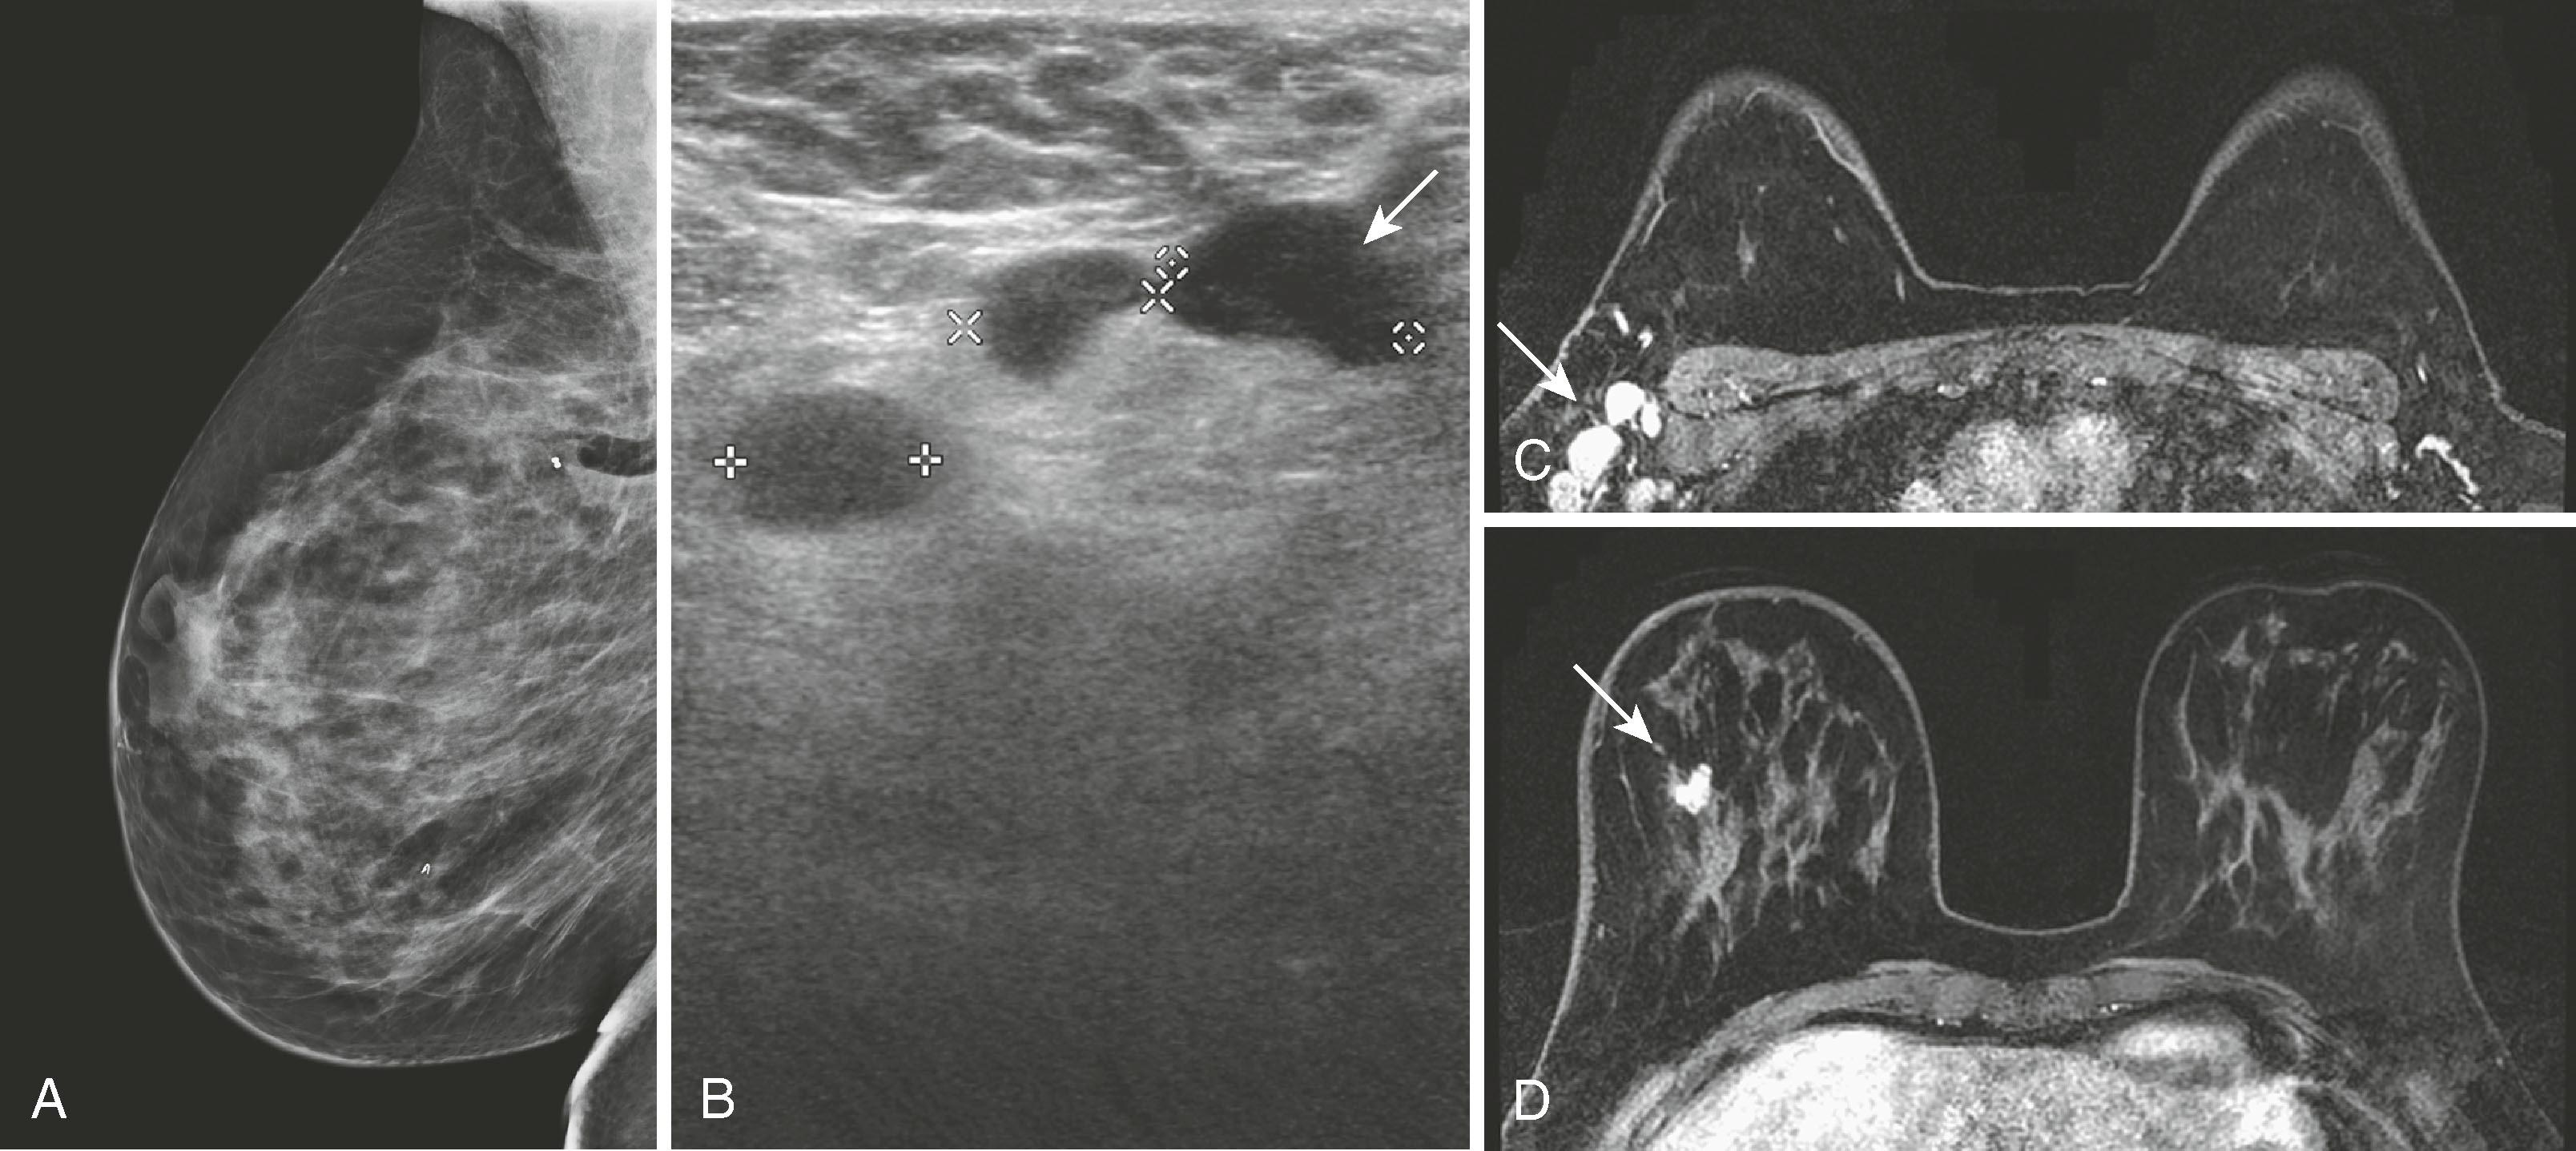

Fig. 8.34, ( A1 and A2 ) Bilateral screening mammography findings are negative. ( B ) Magnetic resonance imaging demonstrates a small enhancing lesion (arrow) in the medial left breast. ( C ) Patient returned for second-look ultrasound, which revealed a hypoechoic lesion with irregular margins (arrow) . Ultrasound-directed biopsy was performed.

Breast MRI has become the gold-standard test to search for a breast primary when a patient presents with a carcinoma of unknown primary. It is valuable not only because of its high sensitivity in identifying the primary tumor but also because of its high negative predictive value. Liberman and associates noted in a small study group of 16 women that MRI identified the primary breast tumor in 13 out of 16 patients. MRI may be of greatest value when a patient presents with axillary lymphadenopathy and a negative mammogram. Fig. 8.35 demonstrates such a patient who presented with axillary lymphadenopathy and a negative mammogram.

Fig. 8.35, A 42-year-old woman was noted to have prominent right axillary lymph nodes and had excisional biopsy of one of the lymph nodes, which revealed carcinoma. Her mammogram did not reveal the primary carcinoma. ( A ) Abnormal mammogram of the right breast. ( B ) Right axillary ultrasound demonstrates enlarged lymph nodes (arrow) . ( C ) Magnetic resonance imaging (MRI) demonstrates the right axillary adenopathy (arrow) . ( D ) MRI additionally demonstrates the occult primary breast malignancy (arrow) .

Not all lesions can be identified by second-look ultrasound, but if they can be identified, ultrasound-directed biopsy is preferable because of its ease and lower cost. DeMartini and coworkers reported that approximately 50% of lesions identified by MRI can be identified by ultrasound, and masses are easier to locate than nonmass-like lesions. Because of differences in breast position (MRI prone and ultrasound supine and decubitus), it is sometimes difficult to be certain that MRI and ultrasound are identifying the same lesion.